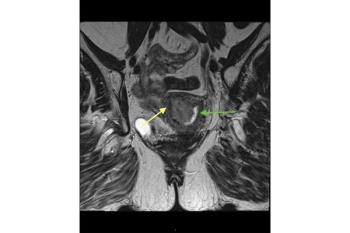

Gadolinium-based intravenous contrast agents (GBCA) provide additional information based on signal intensity changes after GBCA administration.